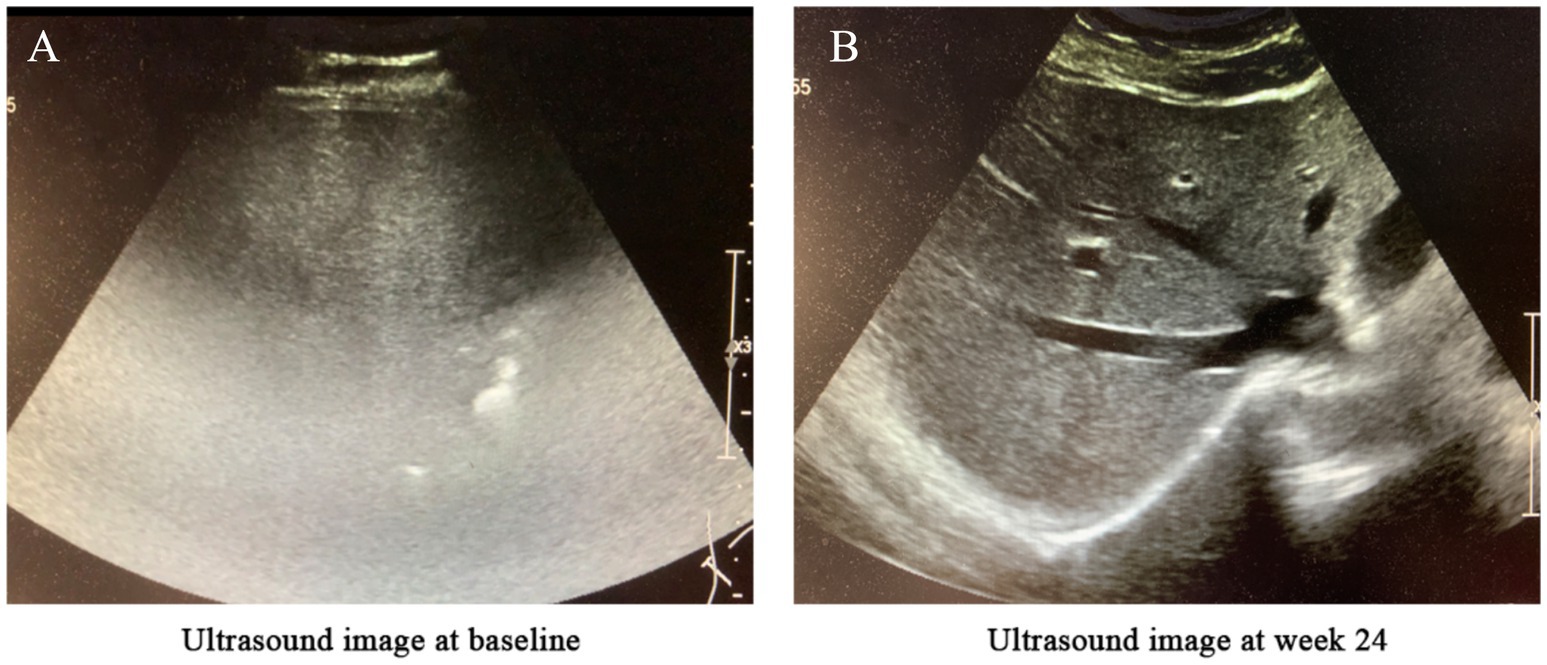

Examinations: Skin biopsy confirmed psoriasis (Figure 1A). Abdominal ultrasound revealed severe MASLD (6) (Figure 2A).

Figure 2

Changes in liver ultrasound imaging before and after treatment. (A) Baseline (before treatment): The hepatic parenchyma exhibited diffusely enhanced echogenicity, with unclear or absent visualization of intrahepatic blood vessels and significant attenuation of far-field echoes. The diaphragm was not visualized, suggesting severe fatty liver. (B) After 24 weeks of semaglutide treatment: The hepatic parenchyma showed diffusely increased echogenicity; however, the diaphragm and intrahepatic blood vessel walls were clearly visualized, indicating mild fatty liver.

Hepatic imaging: Abdominal ultrasound demonstrated reduced hepatic steatosis (Figure 2B).

Regarding MASLD, semaglutide’s benefits were equally notable. The disease’s pathogenesis centers on insulin resistance, hepatocellular lipid accumulation, and chronic inflammation. Semaglutide has been shown to ameliorate hepatic steatosis through weight loss, insulin sensitization, and direct reduction of hepatic fat content (9). In this patient, ultrasound findings confirmed transition from severe to mild MASLD, paralleling improvements in liver enzymes and metabolic parameters.